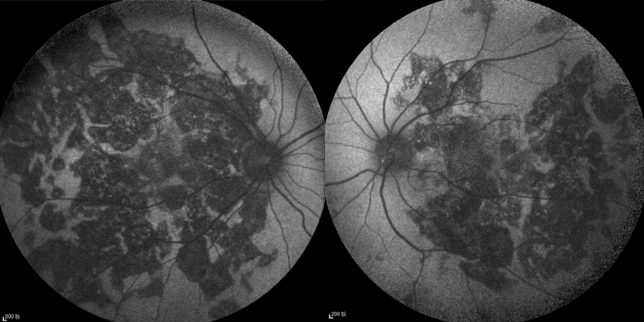

一名21岁的年轻女性,以“双眼视力下降3月余”为主诉就诊,此前已经确诊了SLE ,并且口服激素1年。但其在3月余前无明显诱因出现双眼视力急剧下降,就诊当地医院诊断为“双眼脉络膜炎”,在予药物治疗后无明显好转故就诊于我院。在对其进行眼部体查时可见其右眼裸眼视力为0.25,左眼为0.15,右眼最佳矫正视力为0.8,左眼为0.3。眼底检查双眼视网膜面见大量斑片样脉络膜病灶,自发荧光显示“黑心白边”,病灶围绕视盘,眼底荧光造影显示病灶处有荧光着染,脉络膜造影病灶显示相对应处低荧光。

图片

超广角眼底图

右眼自发荧光图和右眼FFA+ICGA

左眼自发荧光图和左眼FFA+ICGA